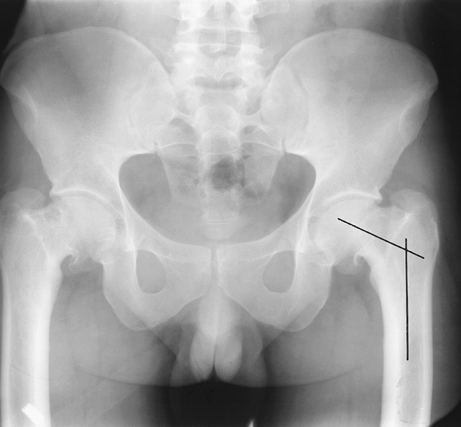

![]() |

FIGURE 4-53 Normal femoral neck angle (lines) seen on AP radiograph.